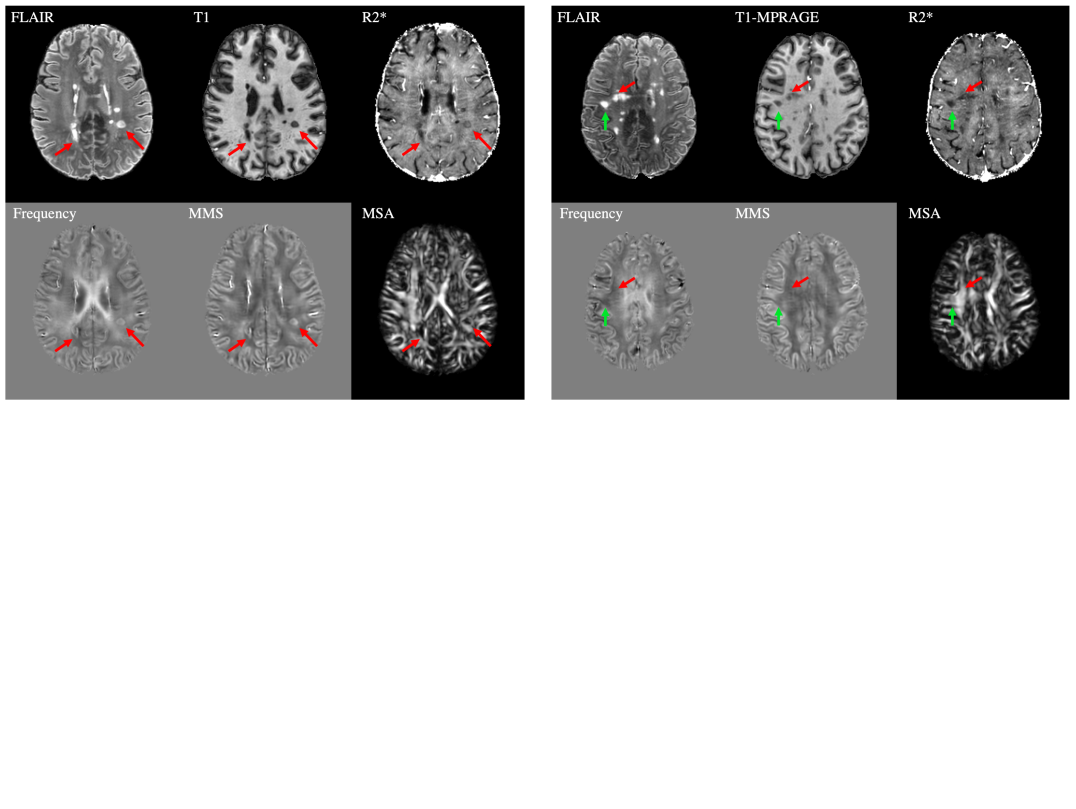

Refer to caption

Figure 8: DeepSTI predicted mean magnetic susceptibility (MMS) and magnetic susceptibility anisotropy (MSA) from MR phase measured at one head orientation in two multiple sclerosis patients .

To further examine the generalization ability of DeepSTI to patients with neurological diseases, we tested DeepSTI using previously published GRE data from two multiple sclerosis (MS) patients (7T data from [42]). Fig. 8 depicts the MMS and MSA maps calculated from DeepSTI using only one head orientation for each patient. For the first patient (Fig. 8.a), DeepSTI predicted increased MMS and decreased MSA in two example lesions that are hyperintense in local frequency (and QSM as noted in [42]) and hypointense in R2* (indicating major demyelination), as indicated by red arrows. For the second patient (Fig. 8.b), two example lesions that appear invisible (isointense) in local frequency (and QSM as noted in [42]), but hypointense in R2* (indicating potential loss of both iron and myelin), and visible in T1 and FLAIR were selected. DeepSTI’s prediction presents isointense in MMS and shows slightly decreased MSA (green arrow) in one lesion, and shows isointense MSA (red arrow) in the other lesion.

Fig. 8 demonstrates the result of our method on two MS patients. While different disease presentations and their neurobiological bases in STI remain to be analyzed in the future, this simple case-study demonstrates that the developed method has the potential to generalize to different clinical settings, e.g. for investigating lesion iron and myelin changes through the measures of MMS and MSA in MS with a single phase measurement. Comparing these results to the positive and negative susceptibility sources using recent chi-separation methods may also be helpful to better interpret the DeepSTI results in MS lesions [15, 69]. Moreover, these results might provide new insights on tissue microstructure changes, such as the manifestation of reduced anisotropy on some MS lesions. We believe this illustrates the potential of DeepSTI to study similar neurological disorders in the future.